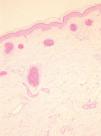

A nivel histológico se observa una epidermis normal junto con una dilatación y proliferación de los capilares en la dermis superficial (fig. 3).

Fig. 3.--Numerosos capilares dilatados y con paredes engrosadas en la dermis superficial.

El estudio anatomopatológico revela la existencia de numerosos capilares dilatados y con las paredes engrosadas en la dermis superficial sin la presencia de inflamación, hemorragia ni hemosiderina 6,7.